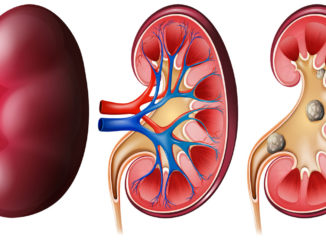

Ledviny jsou vitálním orgánem v lidském těle, který hraje klíčovou roli při filtrování krve a odstraňování škodlivých látek. Když ledviny selžou nebo jsou nemocné, může to mít vážné důsledky pro celkové zdraví. Rozpoznat příznaky nemocných ledvin je důležité, protože rychlá diagnóza a léčba mohou zabránit závažným komplikacím, říká doktor Kevin Martinez. Zde je přehled některých důležitých příznaků, které byste neměli ignorovat. Zvládne je rozpoznat každý.

Jedním z prvních známek problémů s ledvinami může být otok, zejména v obličeji, rukou, nohách nebo kotnících. Ledviny mají za úkol regulovat tekutiny v těle, a když nefungují správně, může docházet k zadržování tekutin, což vede k otokům.

Vysoký krevní tlak (hypertenze) může být důsledkem poškozených ledvin. Ledviny hrají klíčovou roli při regulaci tlaku krve, a když jsou nemocné, nemohou tento úkol plnit efektivně.

Dejte pozor na jakékoliv změny v moči, jako je častější nutkání na močení, tmavá moč, pěna v moči, bolest při močení nebo potíže s močením. Tyto příznaky mohou naznačovat problémy s ledvinami a krev vyskytující se v moči.

Druhou funkcí ledvin je pomáhat při tvorbě červených krvinek, které roznášejí kyslík po celém těle. Úbytek červených krvinek se nazývá anémie. Způsobuje únavu, sníženou výdrž, někdy závratě nebo problémy s pamětí. Únava způsobená onemocněním ledvin může být také zapříčiněna nahromaděním metabolického odpadu v krvi.

Ztráta chuti k jídlu je běžná u lidí s pokročilým onemocněním ledvin. To může vést k podvýživě a ztrátě hmotnosti. Lidé trpící onemocněním ledvin by si měli promluvit s poskytovatelem zdravotní péče o vhodných potravinách, které poskytují potřebné živiny.

Svědění kůže a výrazná suchost mohou být příznaky, které nejprve nejsou spojovány s ledvinami, ale mohou být indikátory potenciálních komplikací. Problémy s ledvinami mohou vést k hromadění toxických látek v krvi, které ledviny normálně odstraňují.

Bolest lokalizovaná v oblasti beder nebo břicha může být další známkou potenciálních potíží s ledvinami. Ledviny se nacházejí v bederní oblasti těla, a pokud jsou postiženy, mohou způsobit nepříjemné bolesti v této oblasti.